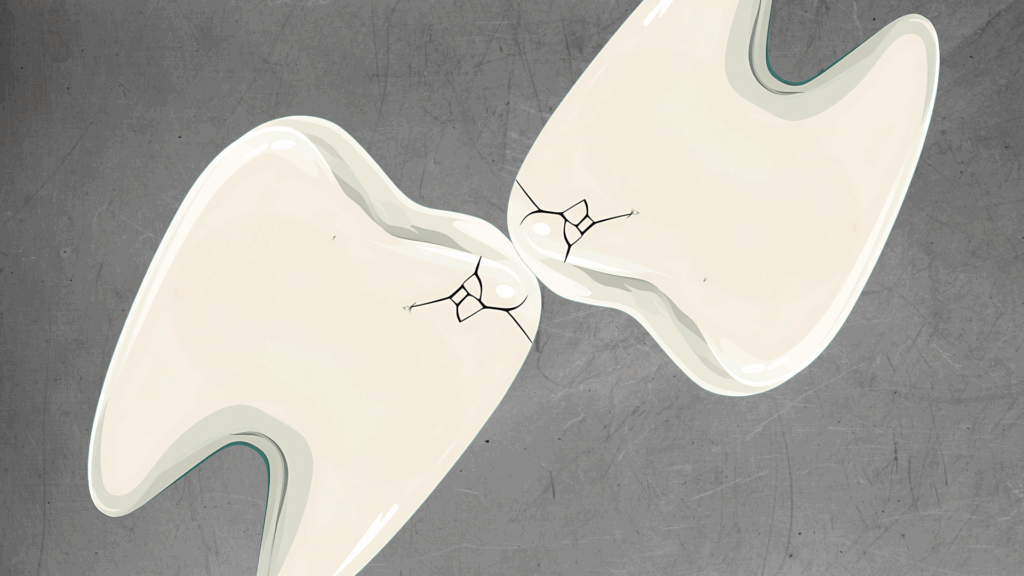

それが、今回のテーマである『歯のヒビ(マイクロクラック)』です。

そう驚かれる方がほとんどです。それも無理はありません。なぜなら、このヒビは肉眼ではほとんど見えないレベルの細かさだからです。しかし、この小さな亀裂こそが、将来的に歯を失う原因になりかねないリスクであることを、皆さんに知っていただきたいのです。

1. 肉眼では見えない『マイクロクラック』の正体

まず、歯の構造について少し触れましょう。歯の表面は『エナメル質』という、人体の中で最も硬い組織で覆われています。水晶と同じくらいの硬度があると言われていますが、硬いということは、逆に言えば「衝撃で割れやすい」という性質も持っています。ガラスをイメージしていただくとわかりやすいかもしれません。

毎日食事をし、噛み合わせることで、歯には想像以上の負担がかかり続けています。長い年月をかけて、硬いエナメル質には目に見えないほどの細かい亀裂が入っていきます。これを歯科用語で『マイクロクラック』と呼びます。

年齢とともに増える『歯の年輪』

正直に申し上げますと、マイクロクラックは誰にでもあります。 私たち人間も、年齢を重ねれば肌にシワができるように、歯にも経年変化としてのヒビが入ります。40代、50代と年齢を重ねるにつれ、マイクロクラックの数は確実に増えていきます。これはある種、歯が頑張って働いてきた証(年輪)のようなものであり、すべてのヒビが悪さをするわけではありません。

しかし、問題なのは『病的なヒビ』です。 通常の経年変化を超えて、深く、鋭く入ってしまったヒビ。これが、痛みやむし歯、最悪の場合は『歯根破折(歯が根元から割れる)』を引き起こす原因となります。

想像してみてください。硬いガラス(エナメル質)に、何十キロもの圧力を何時間もかけ続けたらどうなるでしょうか? 当然、ピシッと亀裂が入りますよね。これが口の中で起きているのです。